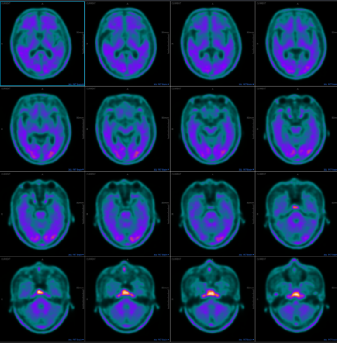

治疗后行PET/CT检查发现:FDG代谢水平表现为多个脑部区域降低,而aβ淀粉蛋白沉积表现在双侧枕叶的视觉空间皮层,对比之前的图像来看,有一定的改善,与患者临床症状表现一致。